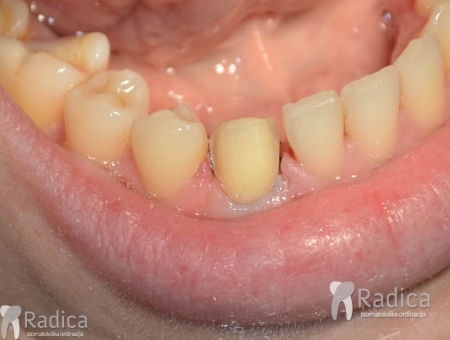

U sljedećem primjeru vidi se mikroimplantat i parcijalni fiksni aparat za otvaranje prostora za smještaj implantata na mjesto izgubljenog donje prvog molara